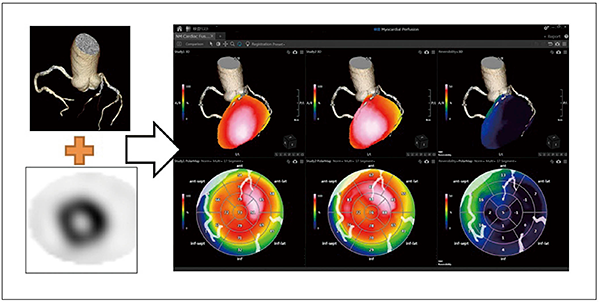

近年,ソフトウェアの進歩により,冠動脈の形態的評価を行う冠動脈CT画像と,機能的評価を行う心筋血流SPECTをフュージョンさせる手法が開発されており,そのフュージョン画像は臨床の場で高く評価されている3),4)。

GCA-9300Rに搭載されるNM Cardiac Fusionも画像フュージョン用アプリケーションの一つで,冠動脈CT画像とSPECT画像の3Dフュージョン表示が可能である。冠動脈の状態(走行・狭窄や石灰化の有無)と心筋血流の状態(虚血・梗塞の有無)を同時に観察することで,責任血管の判定・治療方針の決定・被検者への説明に効果が大いに期待できる(図7)。

また,本アプリケーションでは,ポーラーマップ解析画像も冠動脈CT画像とフュージョン可能で,被検者自身の冠動脈CT画像をオーバーレイ表示することで,複雑な血管走行をポーラーマップ解析画像上でも容易に把握できる。もちろん,ポーラーマップ解析はreversibilityやwashoutといった各種の解析に対応している。

図7 NM Cardiac Fusion使用画像

(データご提供:鹿児島大学様)